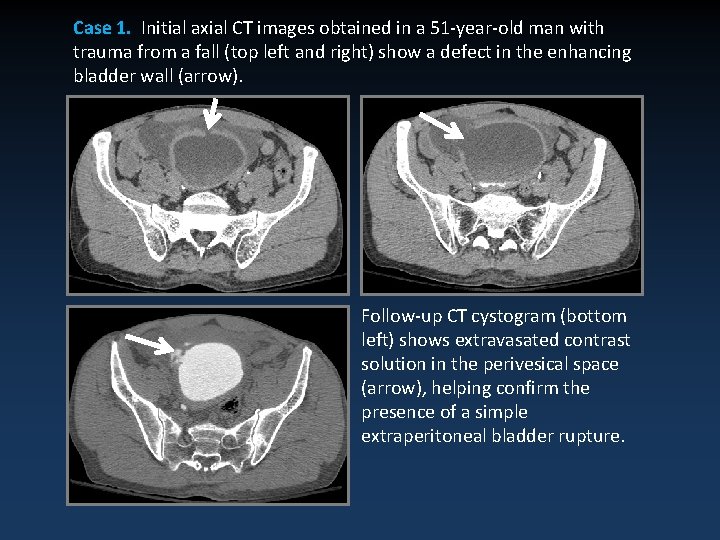

Case 1. Initial axial CT images obtained in a 51 -year-old man with trauma from a fall (top left and right) show a defect in the enhancing bladder wall (arrow). Follow-up CT cystogram (bottom left) shows extravasated contrast solution in the perivesical space (arrow), helping confirm the presence of a simple extraperitoneal bladder rupture.